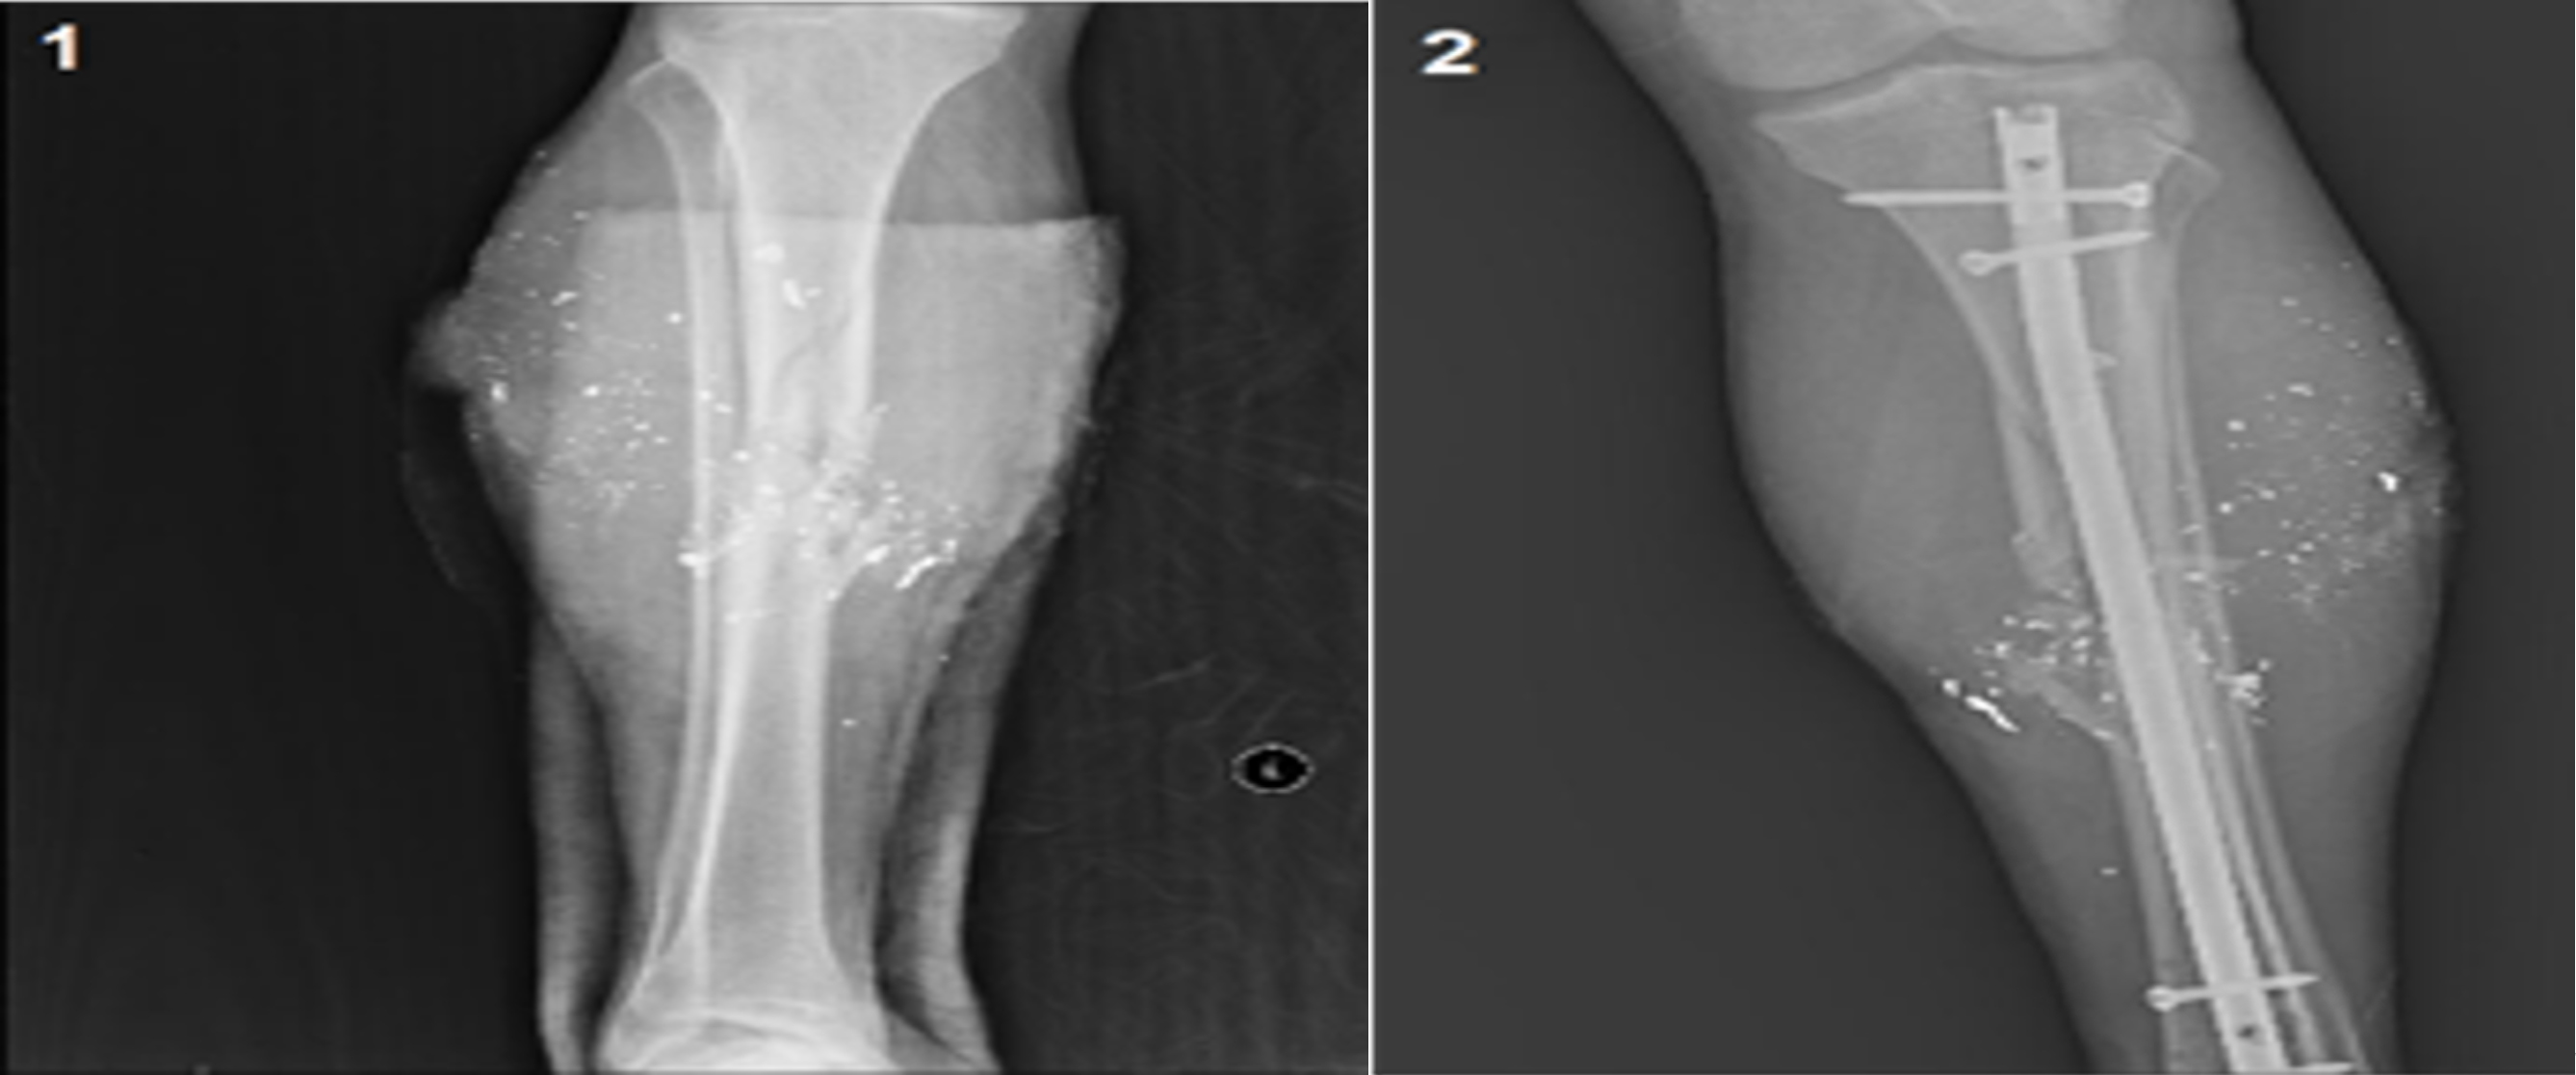

Patient with femoral fractures- Nonunion was observed in a total of 3 patients (6.25%). One of them had osteomyelitis. Union was achieved after pseudoarthrosis surgery in these patients. Delayed union occurred in six patients (12.5%). Union was achieved after dynamization in four patients. Delayed union was associated with deep infection in the other two patients, and union was achieved after infection treatment. Limb shortening was observed in three patients (2 patients with 2 cm, 1 patient with 1 cm) (Table 1). Representative preoperative and postoperative radiographs of tibial fractures treated with intramedullary nailing are presented in Figure 1.

Figure 1. (1); Tibial Fracture - Preoperative Radiograph (2); Postoperative Radiograph of Tibial Intramedullary Nailing